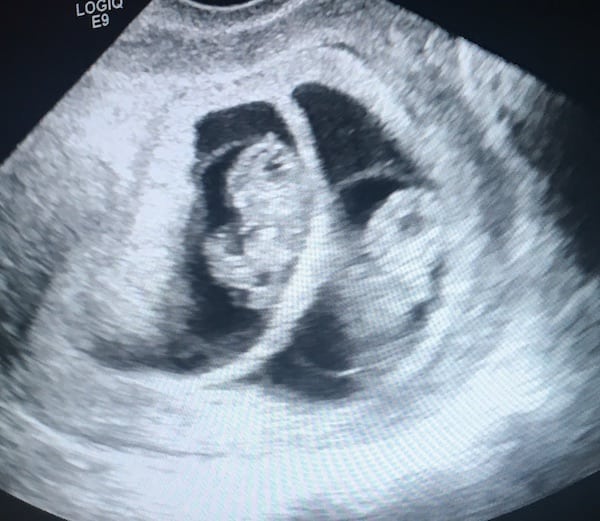

Ultrasound Photos – 8 Week Sonogram

8 week sonogra